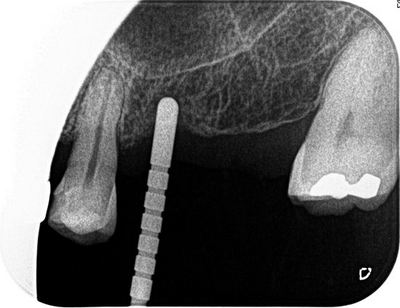

左上臼歯部にインプラント治療を計画します。

オフィス内のCTで撮影して事前にシミュレーションします。

2本のインプラントの埋入を予定します。

深度ゲージを挿入した状態でレントゲンを撮影します。

角度は想定どおりで安堵します。